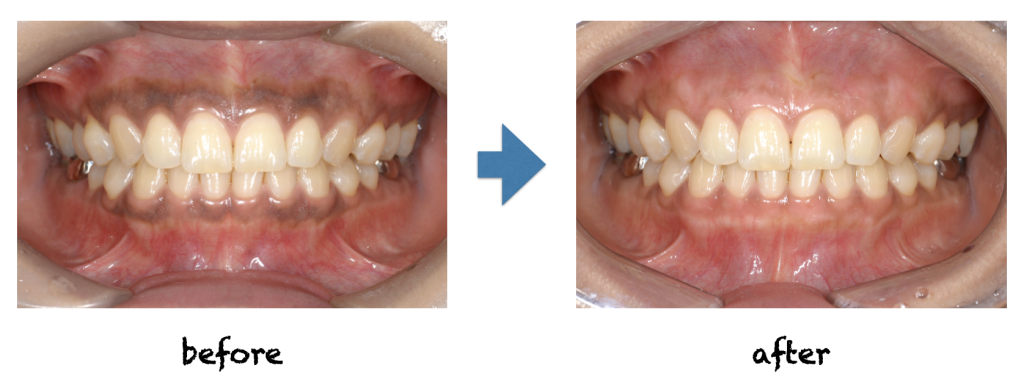

こんにちは! 日中はだいぶ暖かくなってきましたね! 最近は1日の寒暖差が大きいので、体調など崩されないよう、気をつけてお過ごしくださいね! 今回、紹介させていただきますのは、歯肉に重度にメラニン色素が